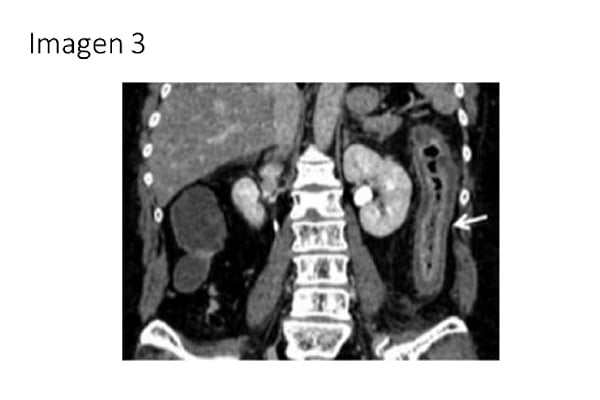

3. Ingresa una paciente de 83 años para tratamiento de aneurisma de aorta abdominal de 50mm de diámetro, por crecimiento rápido en los últimos 6 meses. Entre sus antecedentes destaca: hipertensión arterial, dislipemia, portadora de marcapasos por bloqueo auriculo-ventricular completo como antecedentes. Veinticuatro horas tras la cirugía la paciente presenta distensión, dolor abdominal y rectorragias, acompañado de leucocitosis 32.100µl, con el 95% de neutrófilos y 278 de LDH como únicas alteraciones analíticas, por lo que se realiza un angio-tomografia computerizada, con la siguiente imagen (IMAGEN 3). ¿Cuál es el diagnóstico más probable?:

-

Isquemia mesentérica aguda.

Isquemia mesentérica crónica.

Isquemia mesentérica no oclusiva.

Colitis isquémica.